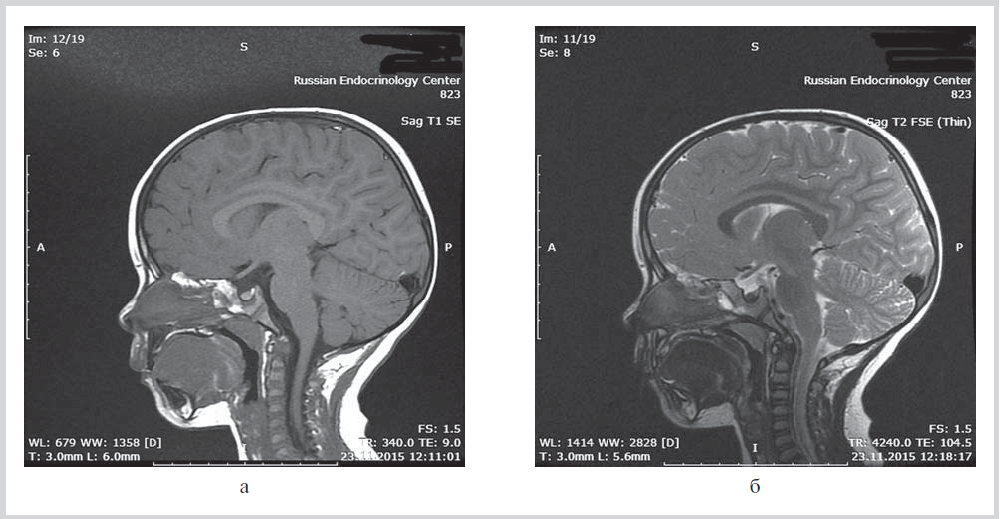

Application of genetic analysis in clinical practice enables identifying a combination of two rare diseases in one patient. We report two cases of patients with hypopituitarism due to PROP1 gene mutations in combination with the 47,XYY karyotype (case 1) and autosomal dominant partial atrioventricular septal defect (case 2). These clinical cases clearly demonstrate that several rare diseases can be present in one patient. The morphology of the pituitary gland has specific features in patients with a PROP1 gene mutation: signal inversion on T1- and T2-weighted images, as well as changes in size of the pituitary gland over time. In case of short stature, the hormonal evidence of secondary hypopituitarism, low IGF-1 levels, and specific morphological features observed in MRI images, we recommended carrying out molecular genetic analysis of the PROP1 gene without conducting growth hormone stimulation test.

4. Рис. 4. МРТ головного мозга пациента 2. | |